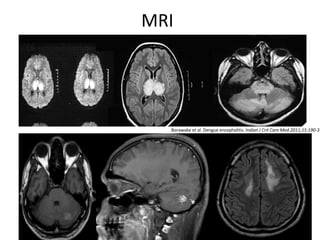

MRI

Borawake et al. Dengue encephalitis. Indian J Crit Care Med.2011;15:190-3

MRI Borawake et al.Dengue encephalitis. Indian J Crit Care Med.2011;15:190-3